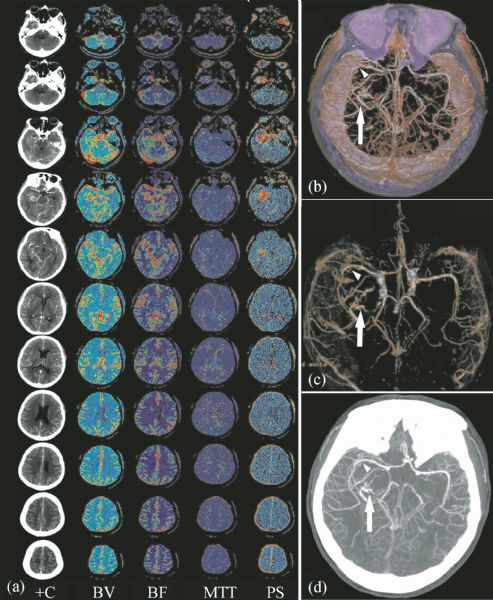

Weiwei CHEN, Jianpin QI, Wenzhen ZHU, Wenhua HUANG, Jinmei SONG

We implemented a new protocol — multiphase dynamic helical scan to acquire CT angiography (CTA) and whole brain CT perfusion (CTP) images simultaneously with single scan on 16 multidetector CT (MDCT). A total of 90 patients who were randomly assigned into 3 groups were included in our study. Each group underwent CT scan by using the new protocol, traditional CTA and CTP protocol, respectively. The image quality of CTA, the CTP parameter values and the X-ray doses were measured and compared between the new protocol and the traditional protocols. There was no statistically significant difference in the CTA image quality between the above methods (P=0.55). For CTP parameters, the new protocol tended to overestimate the blood volume (BV) and blood flow (BF) value, and to underestimate the mean transit time (MTT) value compared with the traditional method. However, there was no statistically significant difference in BV, BF, and MTT value between the two methods except permeability surface (PS) (P>0.05). The volume CT dose index (CTDIvol) and dose length product (DLP) of our protocol were lower than the traditional one. The new protocol can obtain valuable diagnostic information in a shorter time without significant compromise in image quality. In addition, it reduces the radiation dose as well as contrast medium usage on the patient.